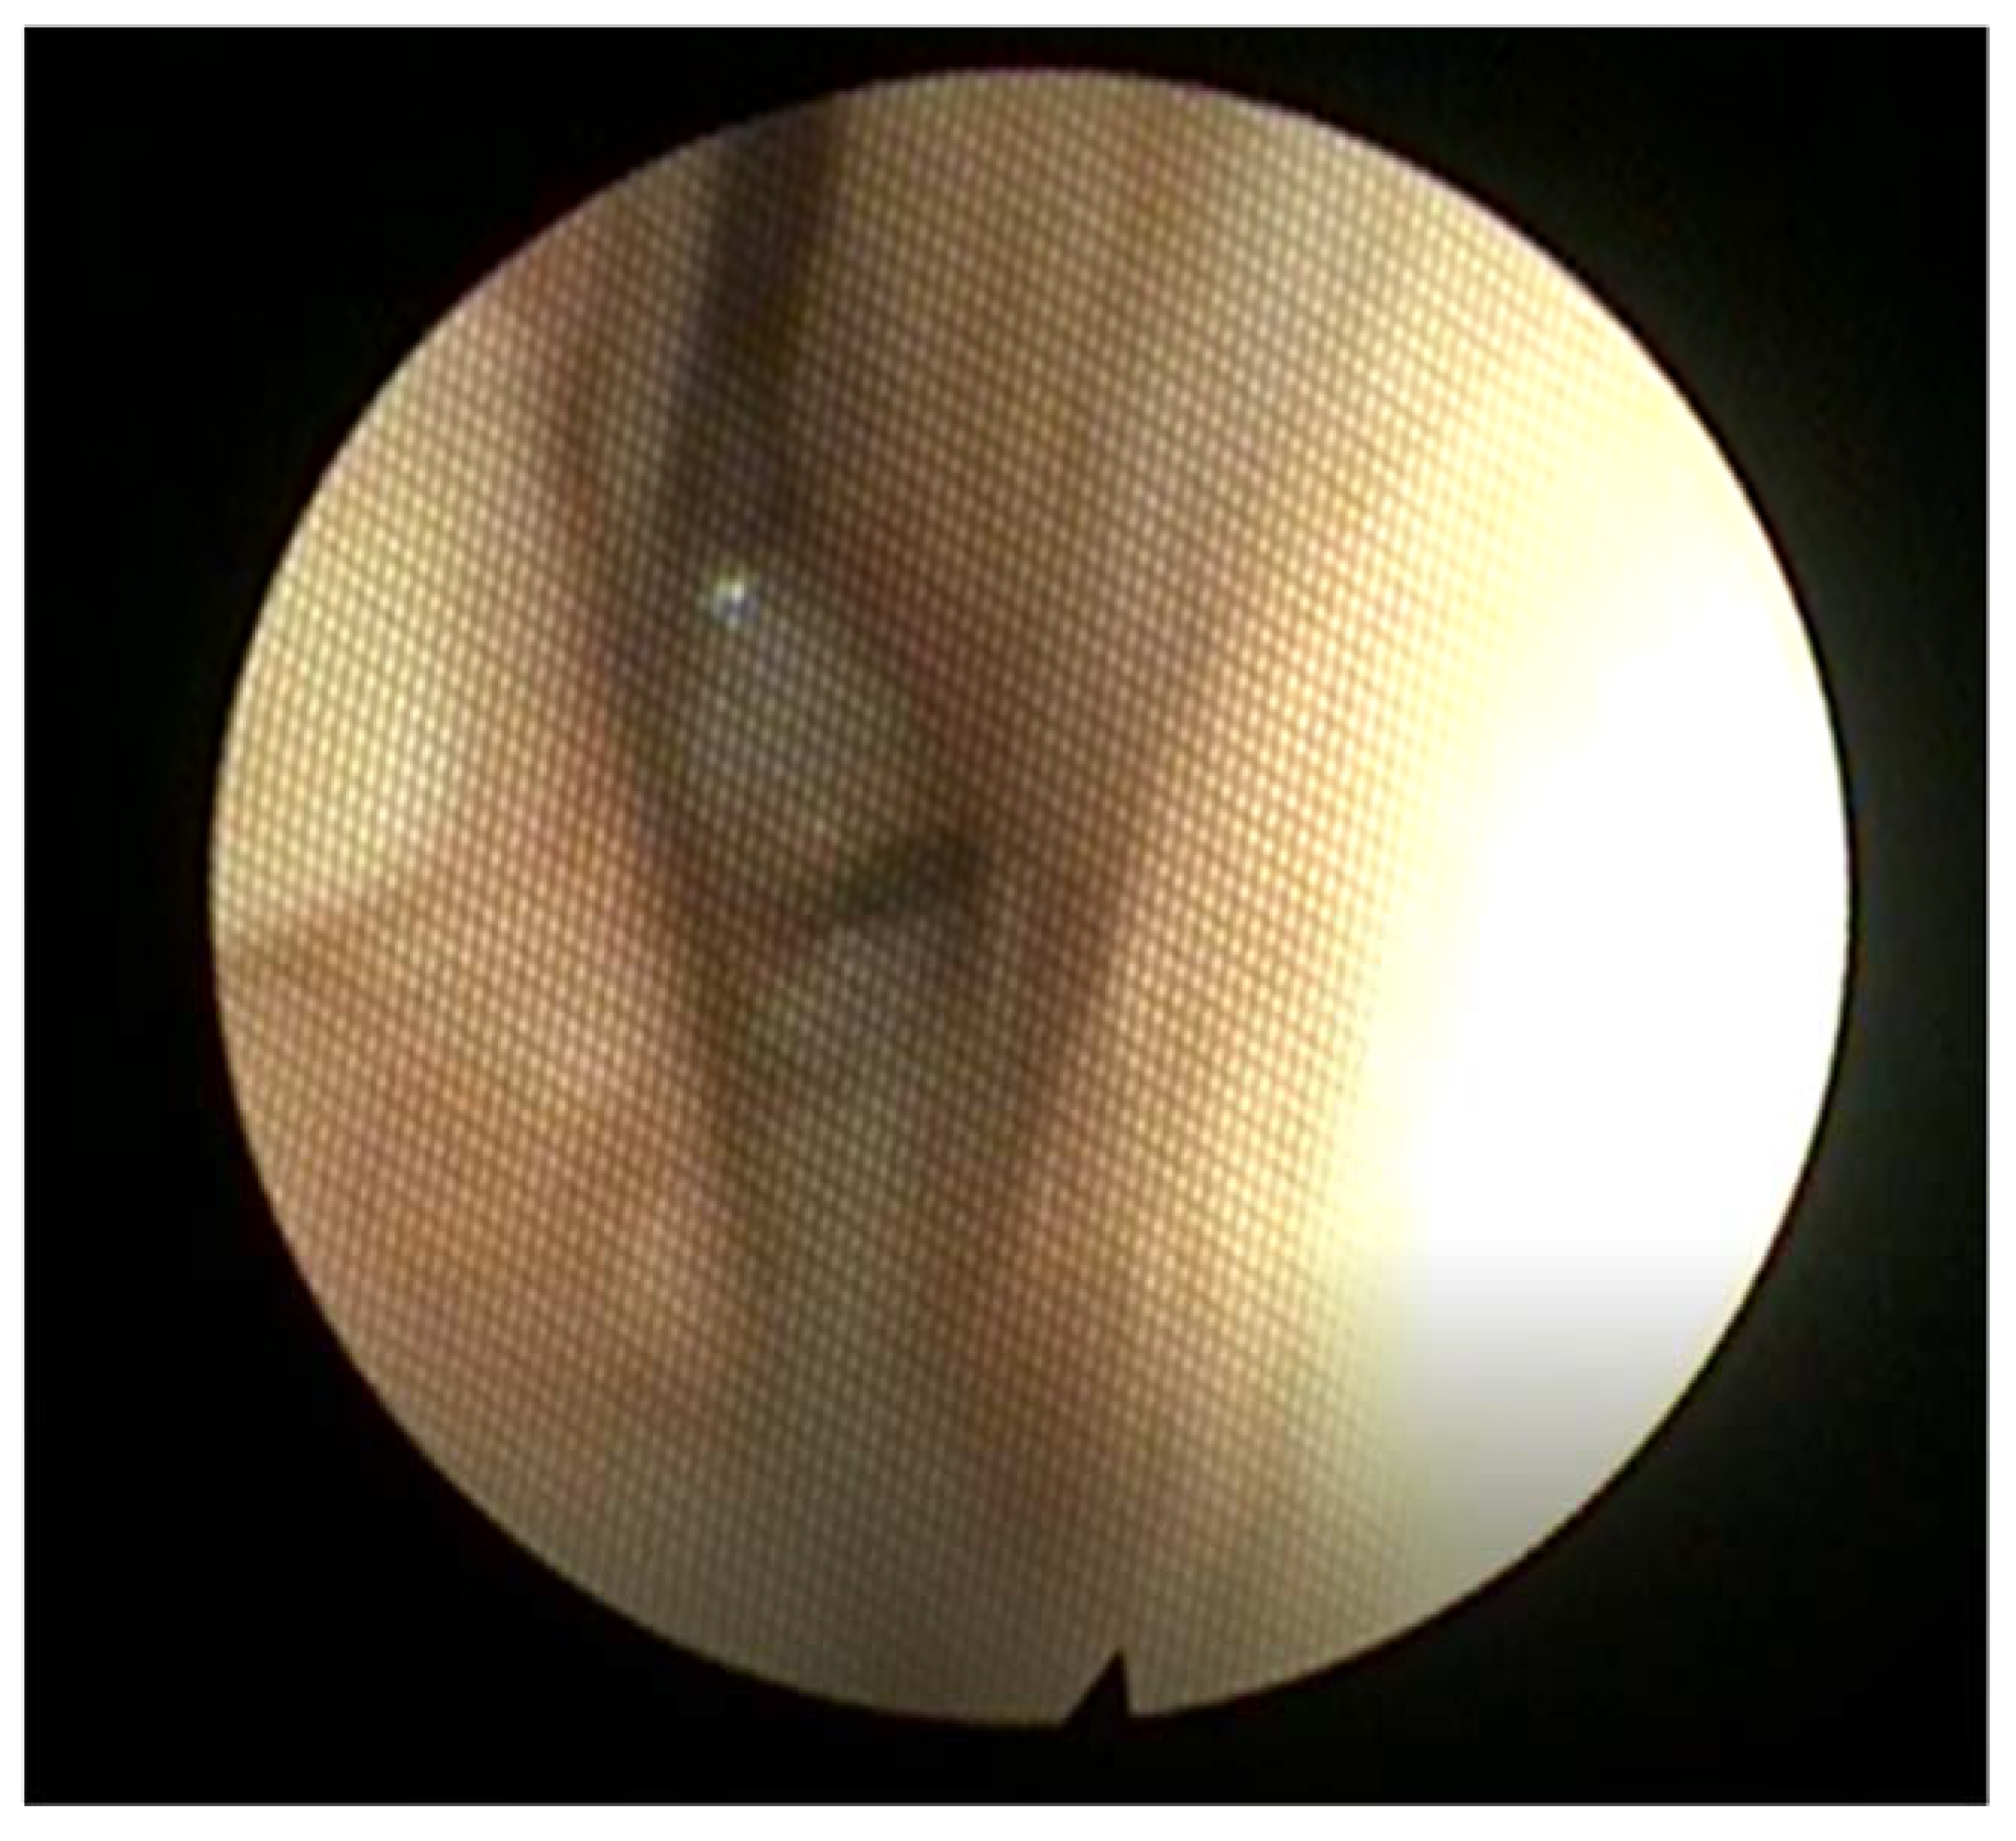

2.12.2. Choanal Atresia

- Attya, H.; Callaby, M.; Thevasagayam, R. Choanal atresia surgery: Outcomes in 42 patients over 20 years and a review of the literature. Eur. Arch. Otorhinolaryngol. 2021, 278, 2347–2356. [Google Scholar] [CrossRef]

- Brown, O.E.; Pownell, P.; Manning, S.C. Choanal atresia: A new anatomic classification and clinical management applications. Laryngoscope 1996, 106, 97–101. [Google Scholar] [CrossRef]

- Ramsden, J.D.; Campisi, P.; Forte, V. Choanal atresia and choanal stenosis. Otolaryngol. Clin. N. Am. 2009, 42, 339–352. [Google Scholar] [CrossRef]

- Gujrathi, C.S.; Daniel, S.J.; James, A.L.; Forte, V. Management of bilateral choanal atresia in the neonate: An institutional review. Int. J. Pediatr. Otorhinolaryngol. 2004, 68, 399–407. [Google Scholar] [CrossRef]

- Strychowsky, J.E.; Kawai, K.; Moritz, E.; Rahbar, R.; Adil, E.A. To stent or not to stent? A meta-analysis of endonasal congenital bilateral choanal atresia repair. Laryngoscope 2016, 126, 218–227. [Google Scholar] [CrossRef]